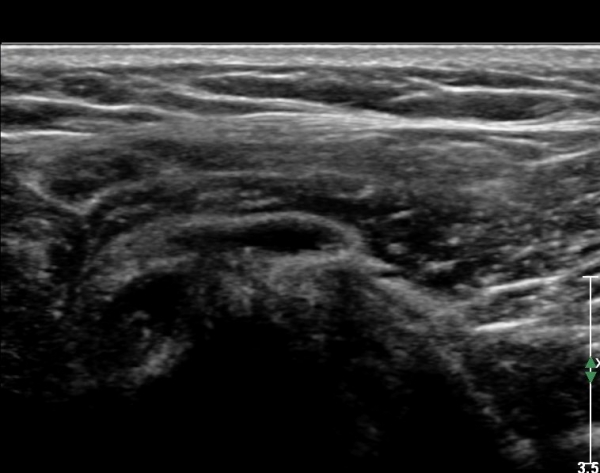

ÃÊÀ½ÆÄ ¼Ò°ß: ¿À±¸µ¹±â¿Í °ßºÀÀ» ¿¬°áÇÏ´Â ¿À±¸µ¹±â°ßº»Àδ밡 Á¤»óÀûÀÎ ¸ð½ÀÀ¸·Î °üÂûµÈ´Ù(»çÁø 1).

ŽÃËÀÚ¸¦ Á¶±Ý ¸»´ÜÀ¸·Î À̵¿ÇÏ´Ï ¿À±¸µ¹±â°ßºÀÀÎ´ë °ßºÀ ºÎÂøºÎ °ñ±ØÀÌ °üÂûµÇ°í Àδë

½ÉÃþºÎ¿¡ ¼ö¾×Àú·ù°¡ ÀÖ¾î ¸¸¼ºÀûÀÎ Ãæµ¹À» ÃßÁ¤ÇÒ ¼ö ÀÖ´Ù(»çÁø 2).